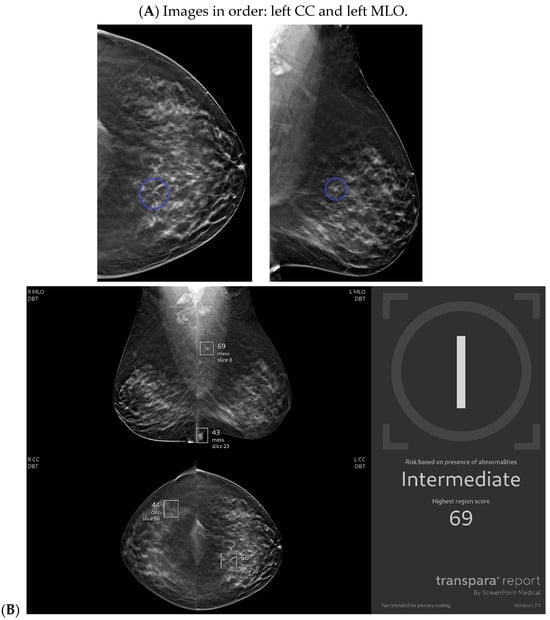

With the widespread implementation of DBT, which increases mammographic cancer detection sensitivity, there are larger volumes of images. This may ultimately increase the risk of reduced accuracy, perhaps due to reader fatigue and increased reading time [24]. There are numerous tomosynthesis AI products available, and at our institution we have implemented the use of Transpara, which is a deep learning-based AI system that uses deep CNN to help improve early-stage cancer detection and sensitivity (at similar specificity), while reducing reading time [24,25]. We view tomosynthesis AI as a valued asset to our clinical practice, as the software highlights potential areas of concern that require additional attention (Figure 1 and Figure 2). However, some areas flagged as concerning are often classically considered benign, such as stable post-lumpectomy sites, stable asymmetries and calcifications, or previously biopsied benign findings. That being said, tomosynthesis AI has been found to have a synergistic effect on cancer detection rate (CDR) when utilized by the radiologist. A study found that radiologist-only CDR was 67.3% and AI-only CDR was 72.7%, but when the radiologist and AI software were used together, the CDR increased to 83.6% [17,25,26]. Lunit INSIGHT MMG, Seoul, South Korea was the diagnostic support software used in this particular study [26].

Figure 2.

New architectural distortion detected by artificial intelligence (AI): A patient in her 50s’ screening mammogram revealed a new area of architectural distortion (circle) in the inner central region of the left breast (A). The AI program Transpara highlighted potential regions of interest, including this suspicious area of architectural distortion on the left breast on the corresponding left CC view; however, AI also highlighted benign areas that were arbitrated out by the radiologist (B). There was no sonographic correlate, so a stereotactic biopsy of this area of architectural distortion was then biopsied under guidance. Pathology yielded invasive lobular carcinoma. Images obtained from the Icahn School of Medicine at Mount Sinai.